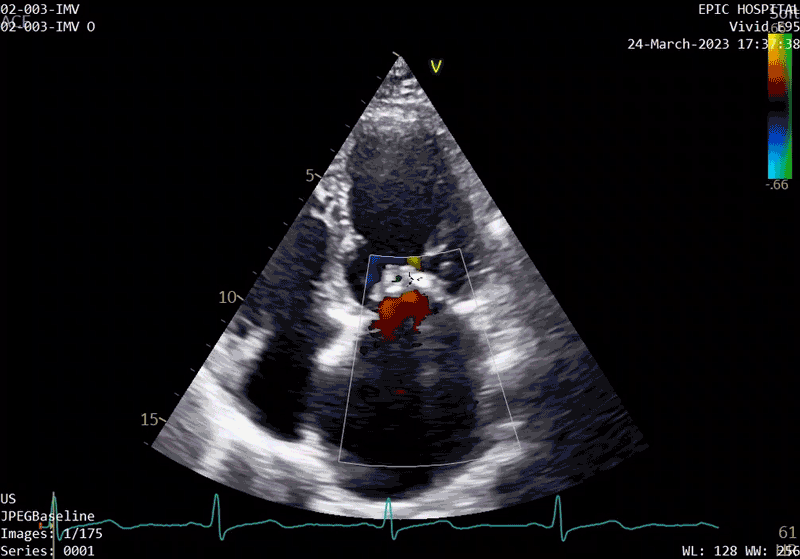

echocardiogram at baseline before surgery

A sample patient echocardiogram at baseline before surgery shows a classic rheumatic mitral valve with stenosis.